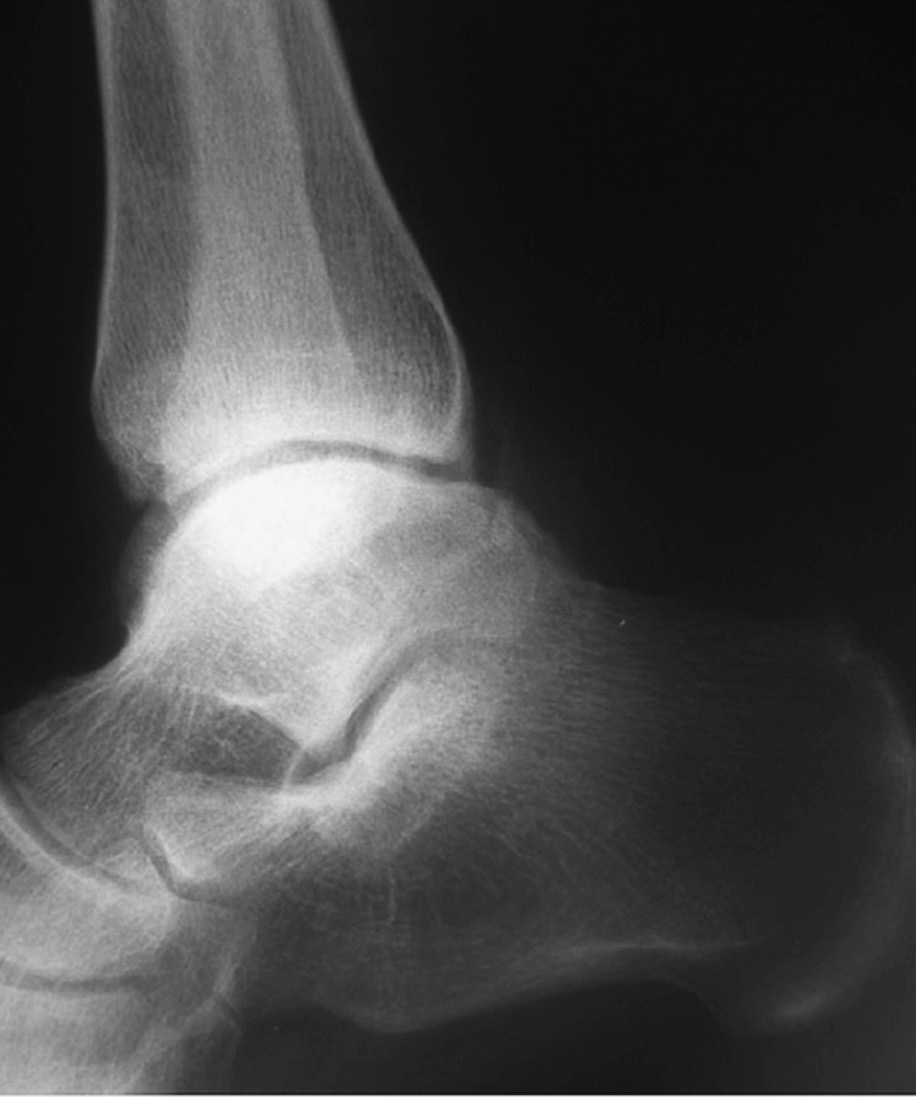

El seguimiento a la largo plazo de las fracturas del astrágalo identifica que la causa más común de los resultados pobres está asociada con la OA subastragalina, tibioastragalina y talonavicular, tanto en nuestra revisión, que alcanzó al 21% (8) de los casos (figs. 9 y 10), como en otros trabajos revisados15,17,19,22,23.

Fig. 9. --A) Fractura del cuerpo del astrágalo tipo B más rotura completa de los 3 ligamentos laterales del tobillo. B) Abordaje bilateral. Osteosíntesis. Sutura de ligamentos. Radiografía y tomografía computarizada a los 18 meses. Artrosis subastragalina y tibioastragalina.

Fig. 9. --a: Type B fracture of the astragalus with complete rupture of the 3 lateral ankle ligaments. b: Bilateral approach. Osteosynthesis. Ligament suture. Radiography and CT at 18 months. Sub-astragalar and tibio-astragalar arthrosis.

Fig.10. --Resultado a los 32 meses. 50° de BA. NAV del cuerpo y artrosis subastragalina y tibioastragalina

Fig.10. --Results at 32 months. BA 50º. Avascular necrosis of the astragalus and sub-astragalar and tibio-astragalar arthrosis.